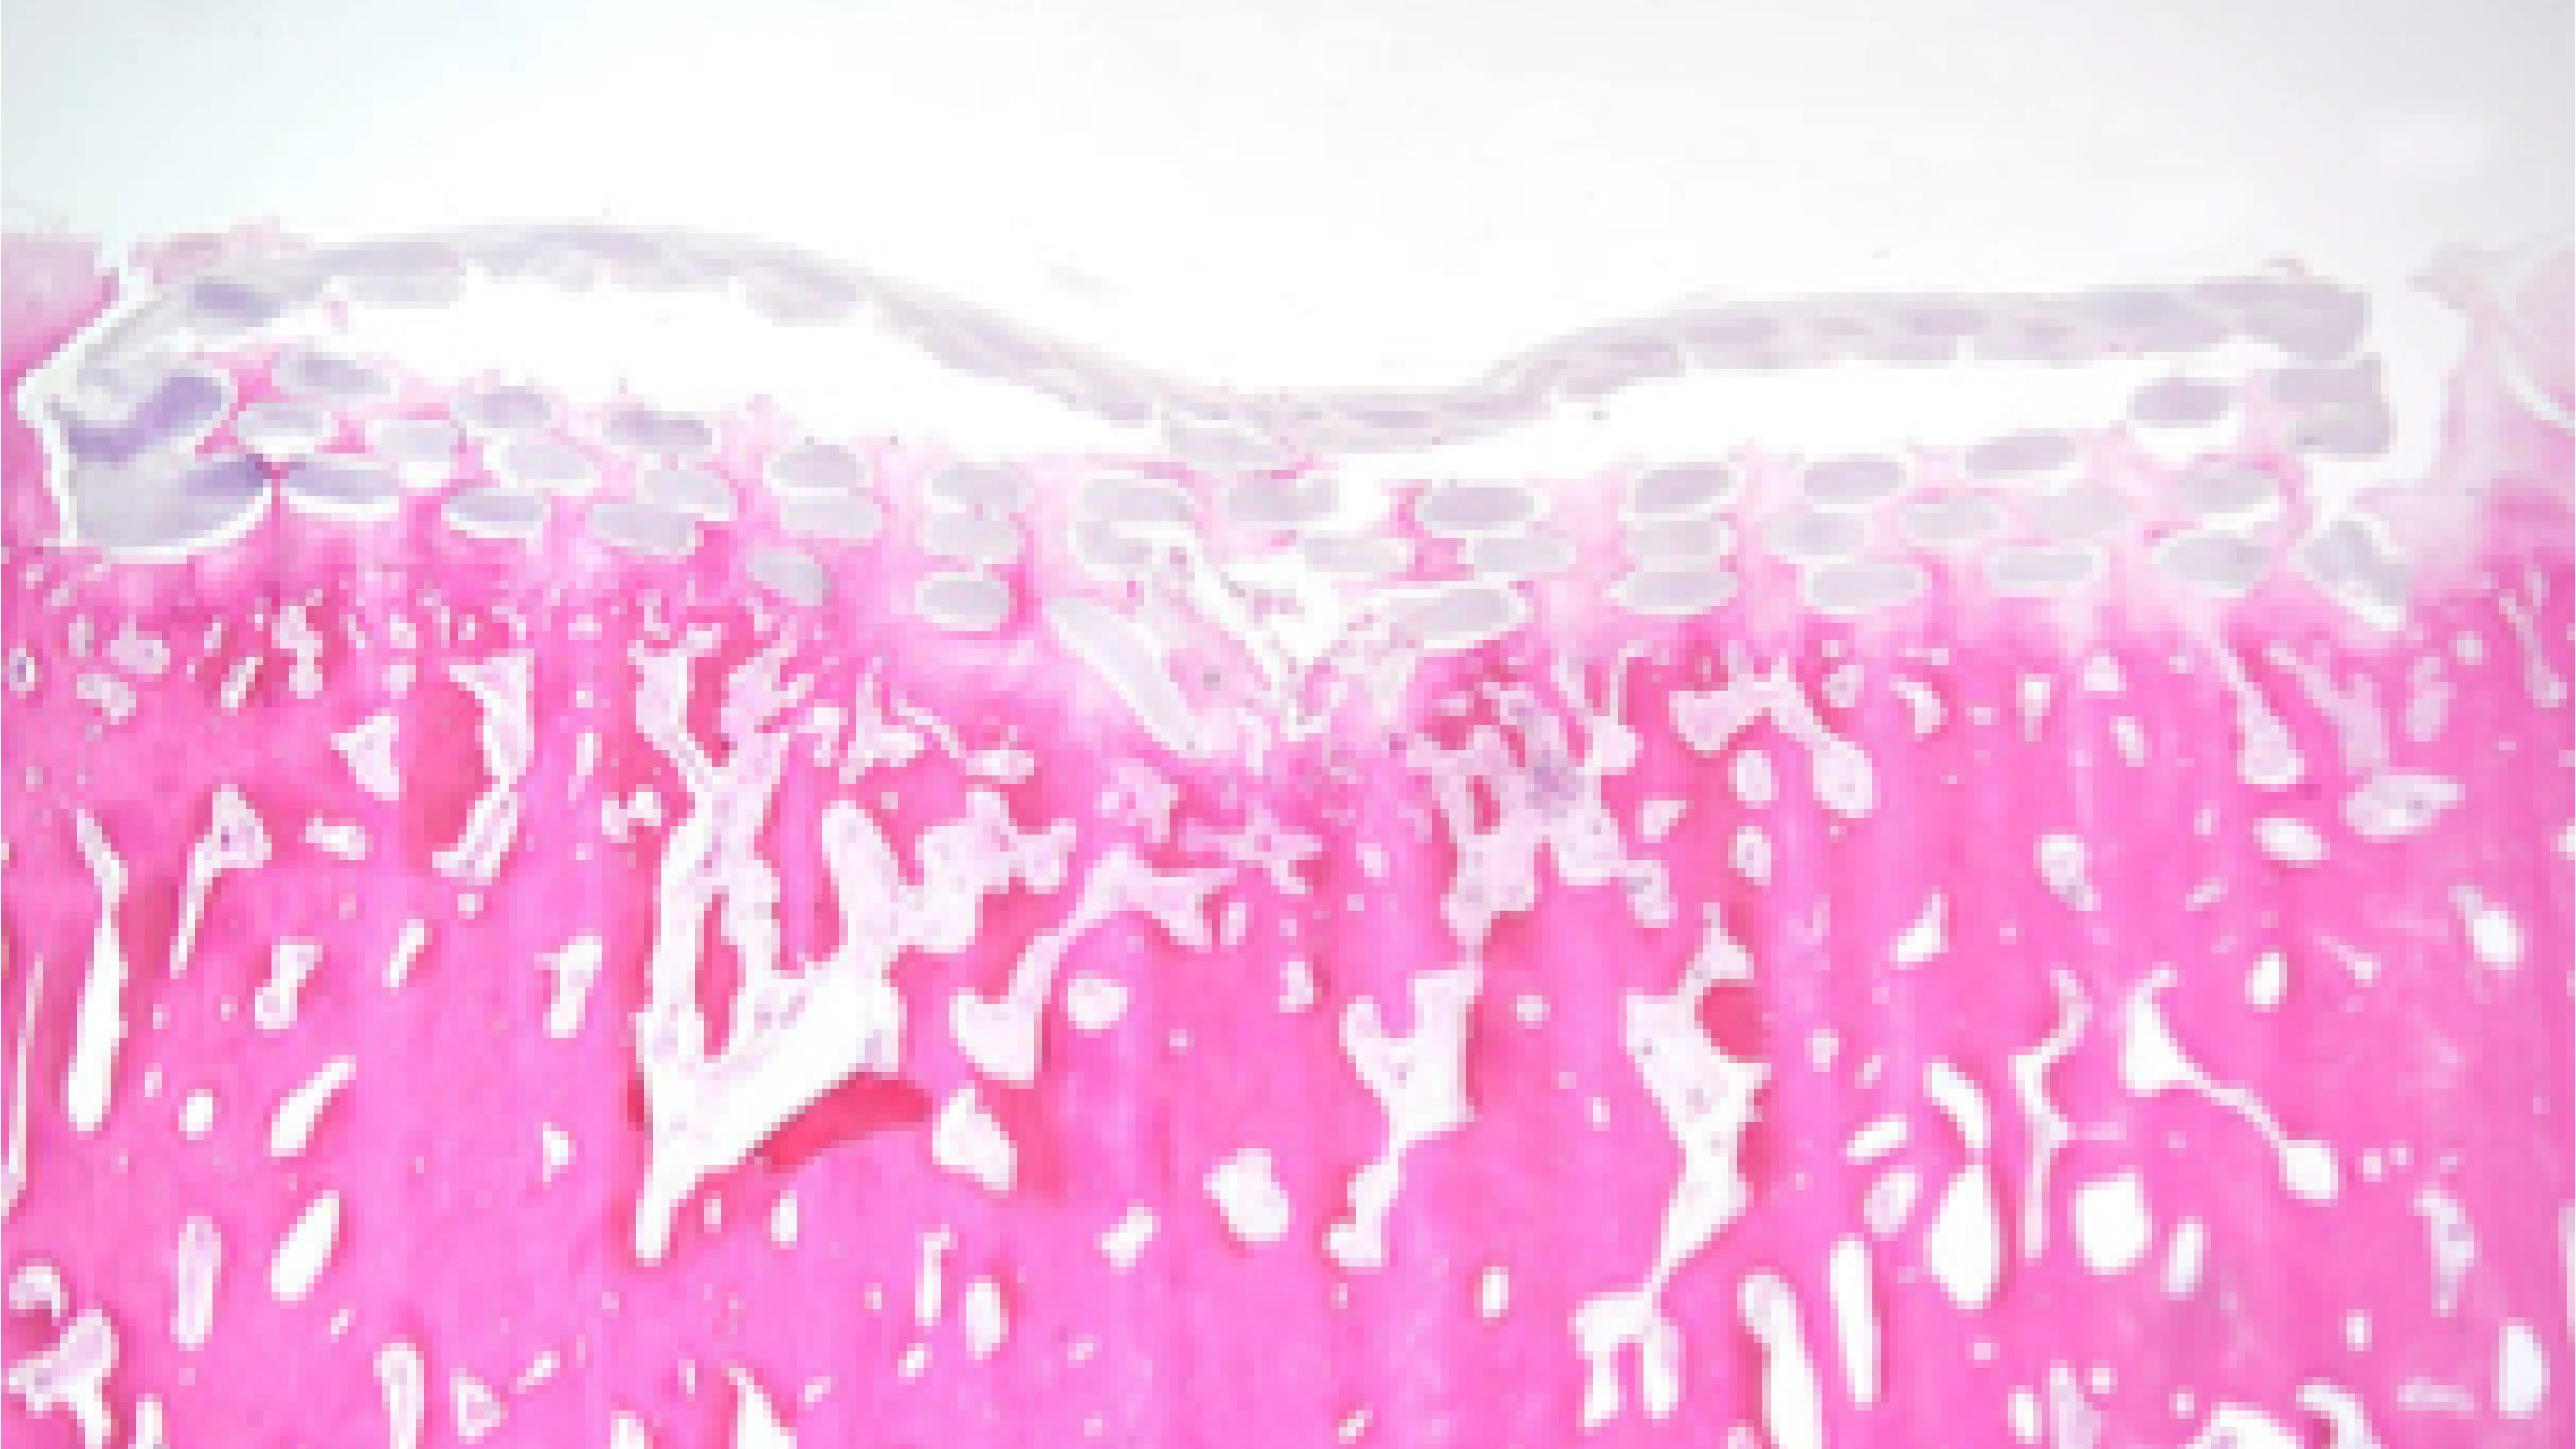

We’ve developed a fully synthetic, nylon-based composite material that mimics the organized collagen fiber structure of natural cartilage. This gives our implant cartilage-matched mechanical properties — low friction, load-bearing, and able to provide immediate mechanical support to the joint.

Unlike traditional methods like injection molding or machining, we use advanced 3D printing to create a complex, highly engineered structure. This design not only offers the strength needed for weight-bearing but also acts as a scaffold, supporting the growth of healthy cartilage and bone tissue over time.